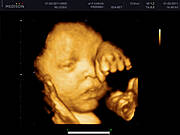

witam wszystkich zaiteresowanych.Ale ten czas leci,jestem już w 32 tygodniu ciąży.Mój synek rośnie(i ja też:) waży już 2kg i rozwija się bez zastrzeżeń pomiomo toksoplazmozy(na szczęście)pozdrawiamy

Jessu jakie piękne Irenko. :):):) Za moich czasów nie było kolorowego Usg az się wzruszyłam.

Moi kochani właśnie trwa 35tydzień,maleńki waży 2500kg a ja o 18kg więcej niż parę miesięcy temu,ale co mi tam jak teraz tak bardzo kochamy jeść:)najważniejsze że synek rośnie zdrowo! nie mogę się już doczekać aż wkleję tu jego foto w realu a puki co muszę wam pochwalić się jak maleńki cycka paluszka w brzuszku:D

Witam wszyskich.Na tę wielkanoc dostałam najcudowniejszy prezent jaki tylko można sobie wymarzyć:)W wielki czwartek przeszedł na świat przez cesarskie cięcie mój ukochany synek Kuba 56cm i 3640kg, 10pkt.dołanczam też zdjęcie bo przeciesz muszę się pochwalić takim przepięknyn prezentem.w czwartek odbieram wyniki na obecność tokso trzymajcie kciuki